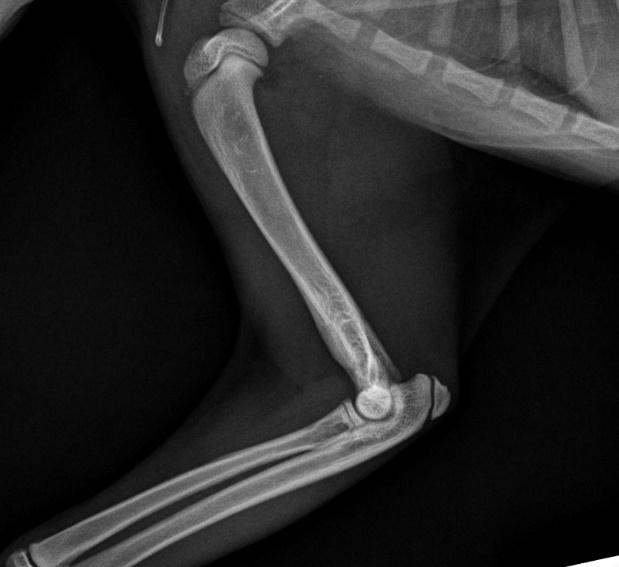

These radiographs are from a 9-month-old cat found by the side of the road ( Figure 1 A&B).

Figure 1. Lateral (A) and DV (B) radiographs from a 9-month-old kitten suspected of having focal osteomyelitis

A. The cat had focal mid diaphyseal osteomyelitis, presumably after penetrating injury, possible after a cat bite wound

B. The cat was started on Amoxyclav (20-25 mg/kg BID), repeat radiographs were planned to monitor the cat’s progress

and lateral (B&C) radiographs from a 9-month-old kitten suspected of having focal osteomyelitis 4 weeks after starting amoxicillin clavulanate

After 4 weeks of Amoxyclav 20-25mg/kg bid (Figure 2 A,B&C) the kitten was clinically normal and non-painful to palpate over the affected area. He was continued on a further 4 weeks of Amoxyclav.

On final recheck and radiograph he was clinically normal and antibiotics were discontinued.